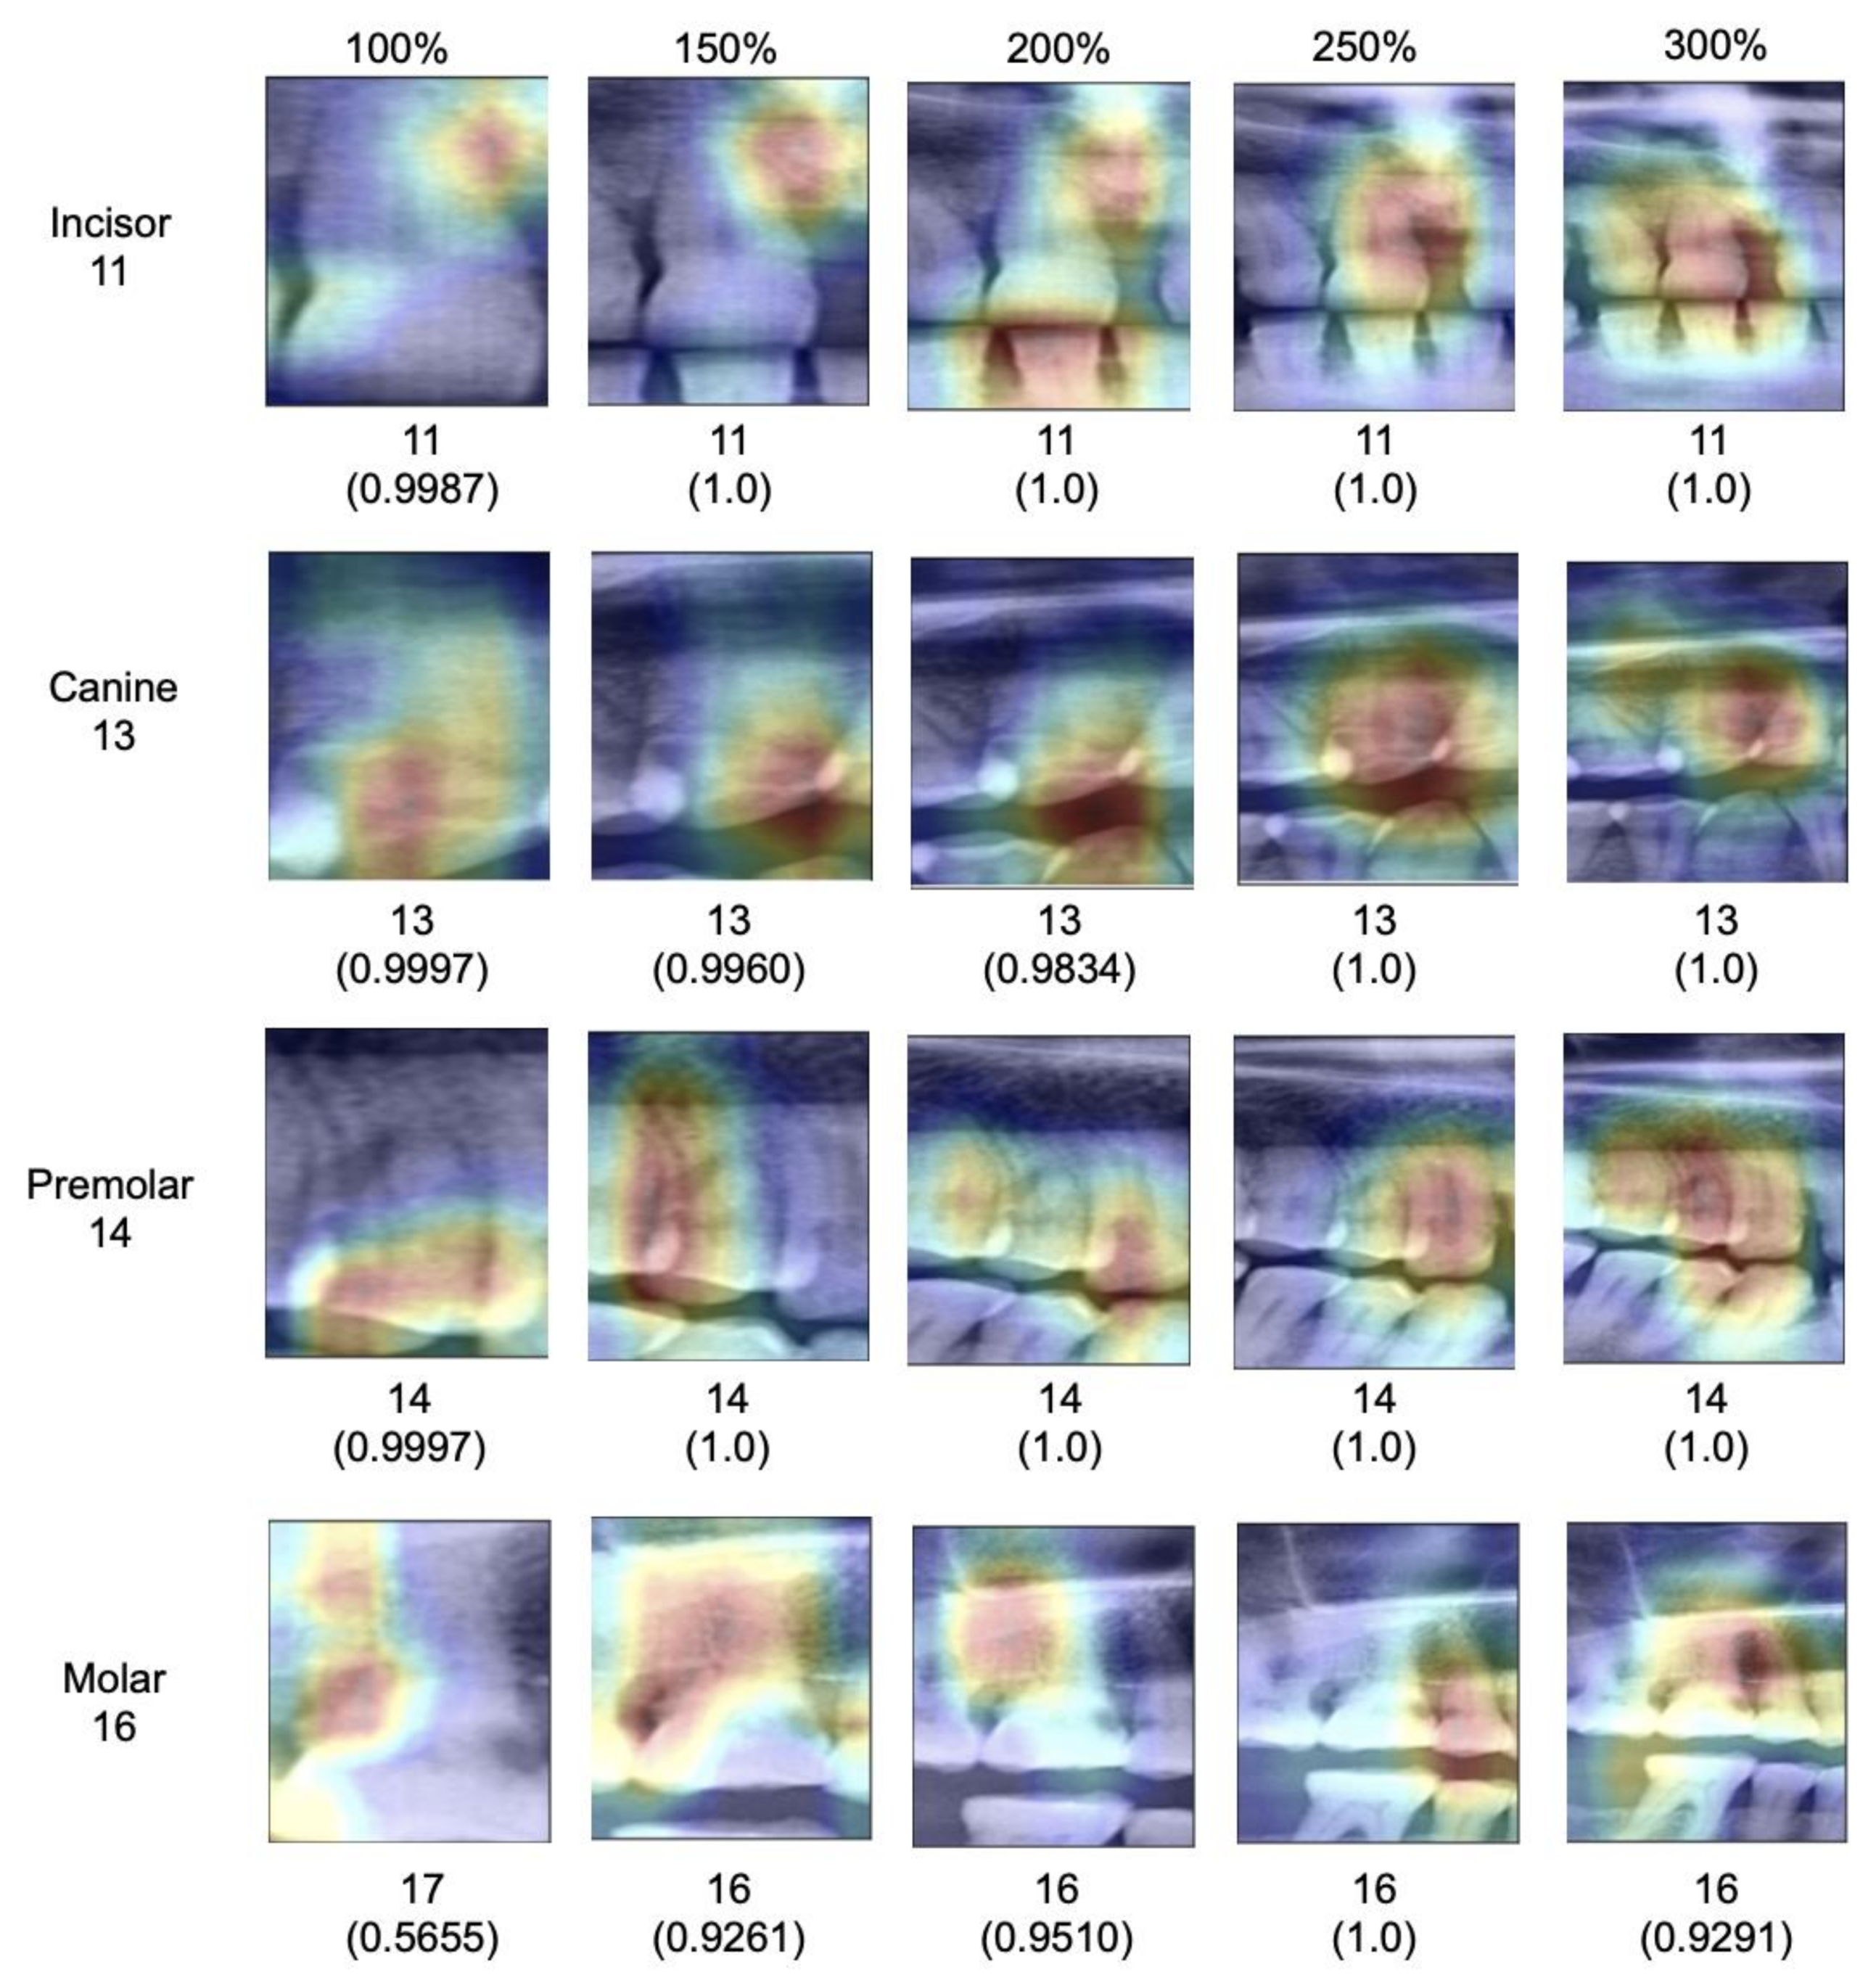

When subgrouping tooth types, it was apparent that for all tooth types except canines and molars, a similar behavior was observed; the F1-score increased monotonically i.e., consistently increased through the extending context of the image segments. The increase flattened from 200% onwards. For canines, accuracy was much higher even for smaller segments and only minimal gains in accuracy reached by increasing context (

Figure 3).

When assessing salient areas relevant for the classification (

Figure 4), we found that with increasing context, the focus was removed from one specific spot of the image (for small segments, this was usually one interdental space or a coronal area of the tooth) and spread broader; at maximum segment size, the models assessed minimum 3–4 teeth as well as the interdental or inter-arch space to come to a classification, obviously making use of the provided context, as hypothesized.

Our findings require a deeper discussion. First, our primary finding can be linked to the fundamental design of CNNs. Early layers of CNNs have the task to detect low-level features such as vertical or horizontal edges derived from changes in brightness within the image. The later layers of CNNs combine these low-level features to detect high-level shapes or objects. Naturally, images with a larger scope of image context provide more low-level features that carry rich information of the image content. Consequently, the model has more possibilities to detect high-level objects, resulting in higher accuracy. Our experiments on explainability confirmed this; the models indeed used the available context in larger segments to come to their classification decisions.

Third, the tooth type played a relevant role for our particular task, tooth classification. While all teeth except canines showed the described behavior, benefitting from context, the classification of canines showed already high accuracy on the baseline image segments and accuracy did not increase with context. This is likely as only one canine can be present per segment regardless of the segment size given the availability of only one canine per quadrant. In this case, misclassification is generally less likely. This highlights one other finding: Based on our findings it seems that models were able to identify each tooth type reliably based on their specific anatomic features regardless of the segment size (e.g., canines seem clearly distinguishable from other tooth types), but that the positioning of the specific tooth type and hence the subclassification (e.g., first versus second molar) required context (which for canines, played no role, as no discrimination from other canines was needed.)